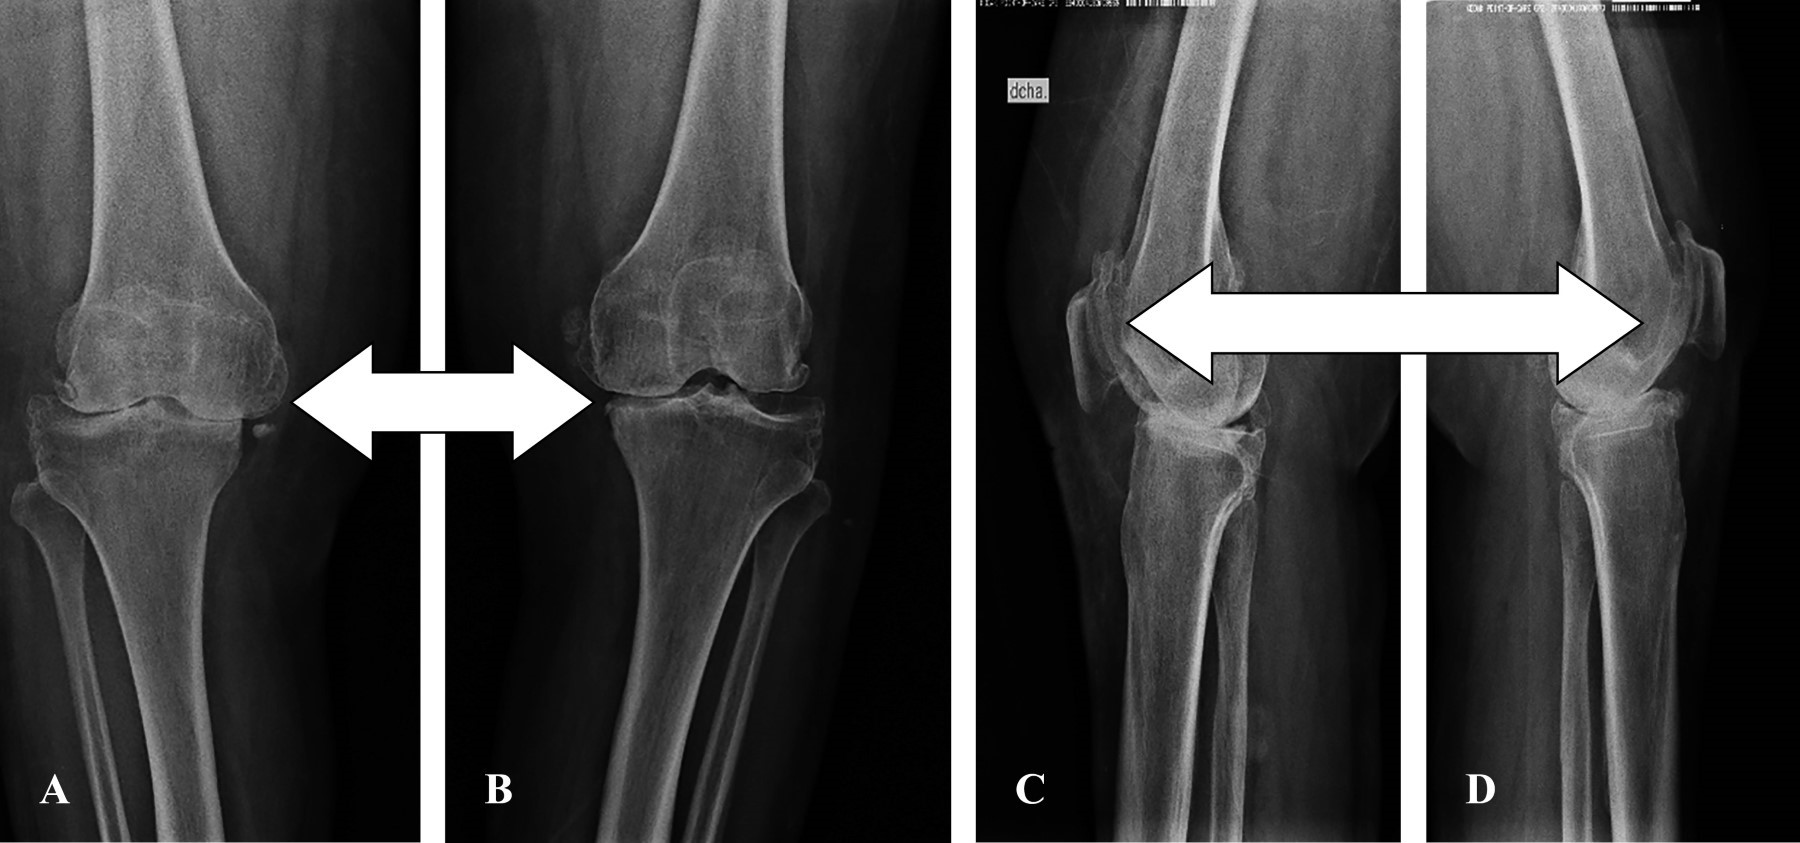

Radiografías previas a cirugía (Figura 6).

Figura 6